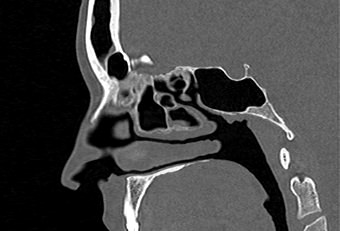

В современной отоларингологии широко применяется мультиспиральная компьютерная томография для диагностики различных заболеваний ЛОР-органов. КТ относится к лучевым методам исследования, который с помощью рентгеновских лучей позволяет получить детальное изображение костных структур, хрящей носа, околоносовых воздухоносных пазух и прилегающих областей.

Преимуществом КТ является ее способность отлично визуализировать кости лицевого черепа, что делает методику незаменимой для оценки любых травматических повреждений носа, выявления аномалий развития носовой перегородки и, деформации хрящей.

Аппараты сканируют область исследования в течение нескольких секунд, производя одномоментно от 64 до 128 тончайших срезов толщиной от 0,5 мм. Высокая скорость сканирования обеспечивает минимальную дозу облучения для пациента. При этом получаются четкие изображения с высоким контрастным разрешением, что дает возможность рассмотреть исследуемую зону в мельчайших подробностях. Кроме того, томографы создают объемные 3D-изображения области носа и прилегающих пазух, что помогает в оценке пространственного соотношения анатомических структур, выявленной патологии и способствует проведению точной диагностики.